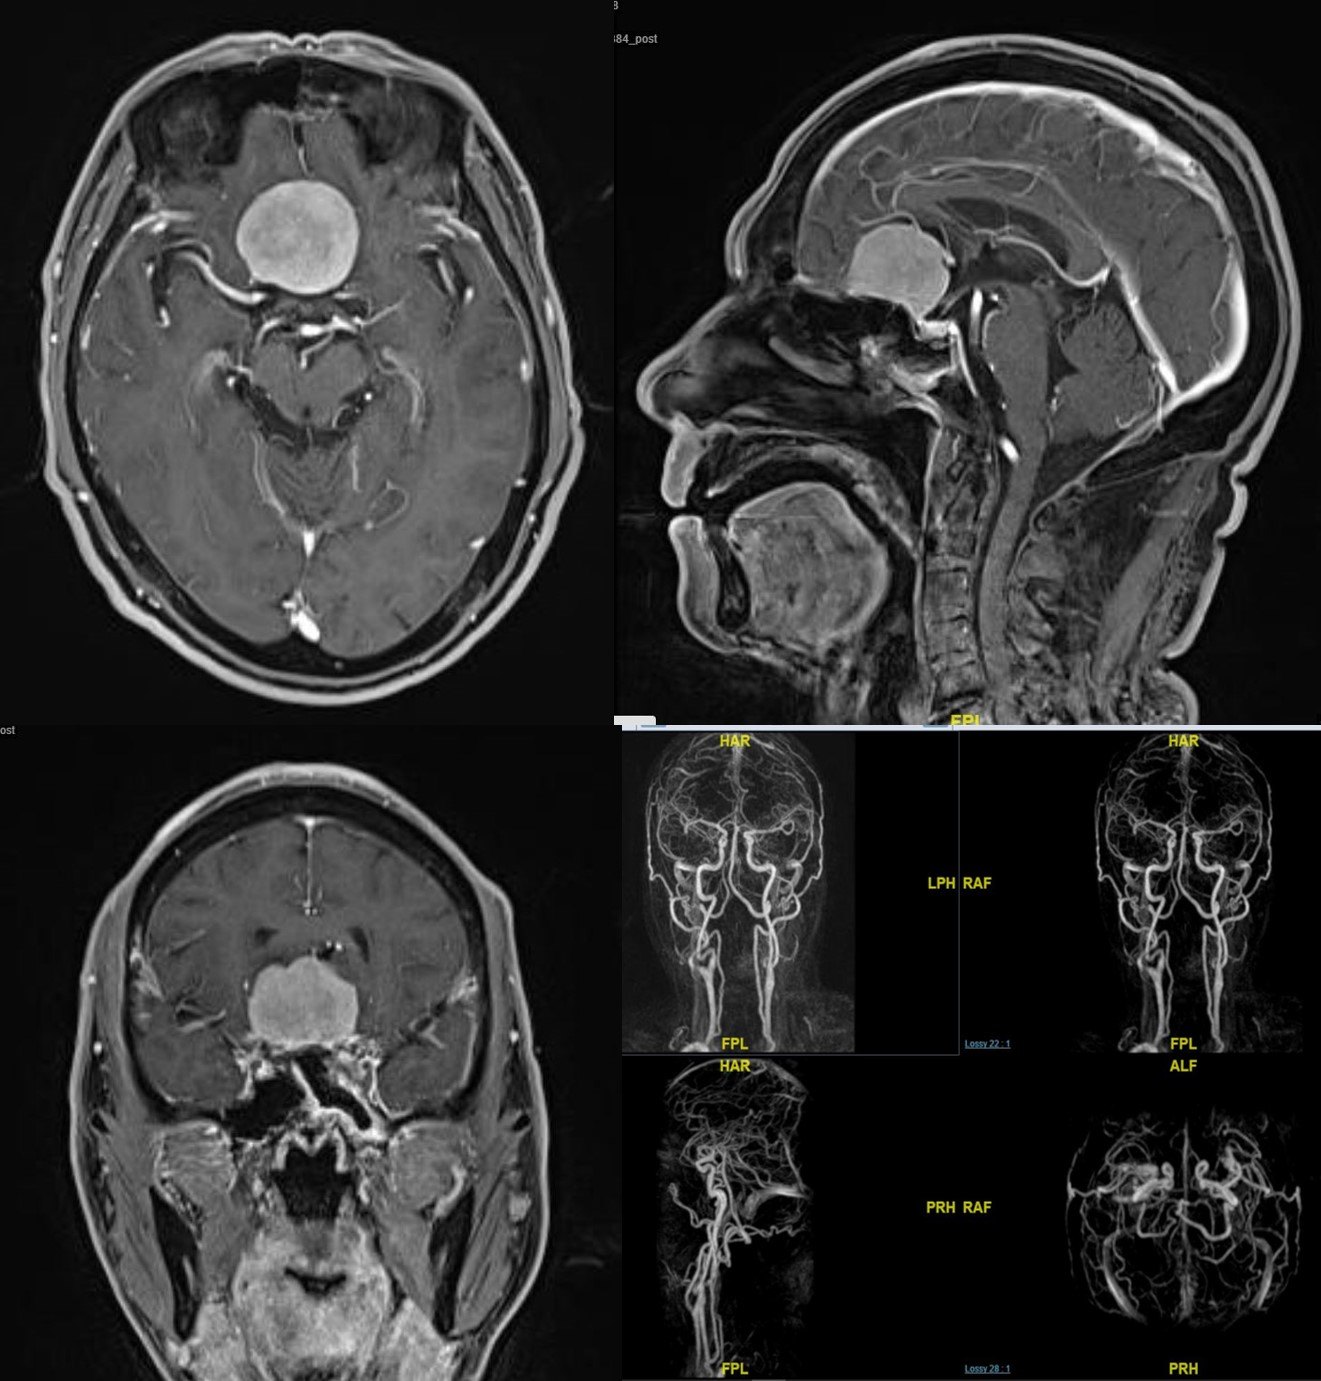

患者男性,62岁,因头痛头晕伴嗅觉减退数年入院。复旦大学附属肿瘤医院神经外科高阳

查头颅MRI示:前颅凹蝶骨平台占位性病变,均匀强化,脑膜尾征明显。

术中可见大脑镰、双侧视神经、视交叉、两侧颈内动脉、嗅神经,垂体柄、鞍隔、蝶骨平台、鞍隔孔及大脑前动脉,神经、动脉完整保留。